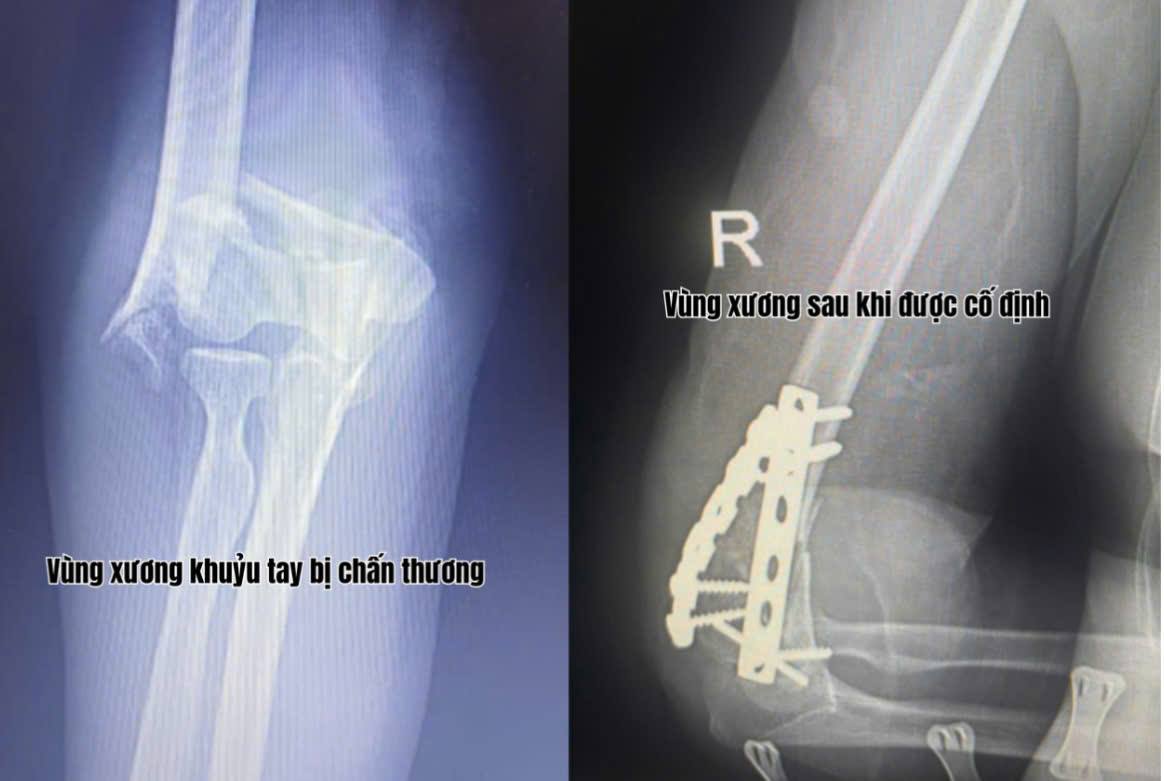

Trong thời gian gần đây, Khoa Ngoại – Trung tâm Y tế Thị xã Quảng Yên liên tiếp tiếp nhận nhiều trường hợp chấn thương vùng cánh tay, khớp khuỷu do tai nạn sinh hoạt và lao động. Các ca bệnh đều có đặc điểm gãy xương phức tạp, tổn thương lan đến khớp, đòi hỏi phẫu thuật chính xác và xử trí kịp thời để tránh biến chứng dính khớp, cứng khớp hoặc mất chức năng vận động.

Trước yêu cầu chuyên môn cao, đội ngũ bác sĩ chấn thương chỉnh hình của Trung tâm, do BSCKII Đỗ Văn Cường trực tiếp phẫu thuật, đã triển khai kỹ thuật kết hợp xương (KHX) vùng cánh tay – khớp khuỷu bằng hệ thống nẹp vít chuyên dụng dưới hỗ trợ của máy C-arm hiện đại.

Việc ứng dụng công nghệ hình ảnh tăng sáng trong mổ giúp định vị chính xác ổ gãy, kiểm soát toàn bộ quá trình nắn chỉnh và cố định, đảm bảo xương được đặt đúng vị trí, khớp được bảo tồn tối đa.

Nhờ kỹ thuật chính xác và quy trình phẫu thuật an toàn, các bệnh nhân sau mổ đều có xương cố định vững, khớp khuỷu vận động sớm, giảm đau nhanh, hồi phục chức năng tốt. Việc tập phục hồi vận động sớm được bác sĩ hướng dẫn ngay tại giường bệnh, giúp hạn chế tối đa nguy cơ teo cơ và cứng khớp.